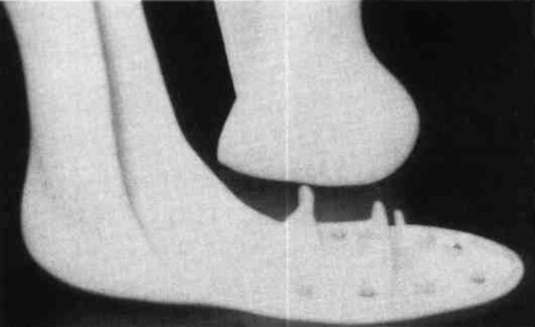

To fabricate one, bulk plaster is poured into a shoe box top to provide a mold. Polypropylene is molded over this. The molded plastic is cut into quarters and the four corner pieces are arranged in such a manner that the corners fit together forming a three dimensional cross shape. Place them onto the anterior "sole" of the prosthesis. Trim to fit the edges of the sole. Rivet the two anterior (left and right) sections to each other and then to the toe section of the prosthesis. Next, rivet the remaining two pieces together and place this section against the anterior shell. Trim and fit it until a 5/8" gap is formed between it and the "anterior box" section. Rivet the remaining loose box section to the sole (Fig. 1). The 5/8" gap between the two "box" sections is filled with foam rubber (Fig. 2). The durometer selected depends on how firm a toe break is desired. This design has provided the more agressive patient with a toe action that simulates the push-off activity of the contralateral foot.

Figure 1. Box sections rivetted in place. Anterior shell shown in the back ground.Figure 2. Foam rubber bumper laying beside forefoot section. Anterior shell in place.